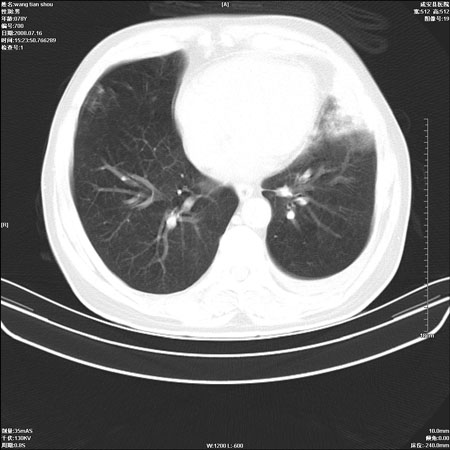

以下是引用qingjing在2008-7-16 19:55:00的发言:[br]1、左上肺不张并堵塞性炎症,建议支气管镜详查;[br]2、左侧胸腔少量积液。

以下是引用wzr在2008-7-16 20:26:00的发言:[br]左肺肺不张伴阻塞性肺炎!另:左侧胸腔少量积液。建议纤支镜检查!